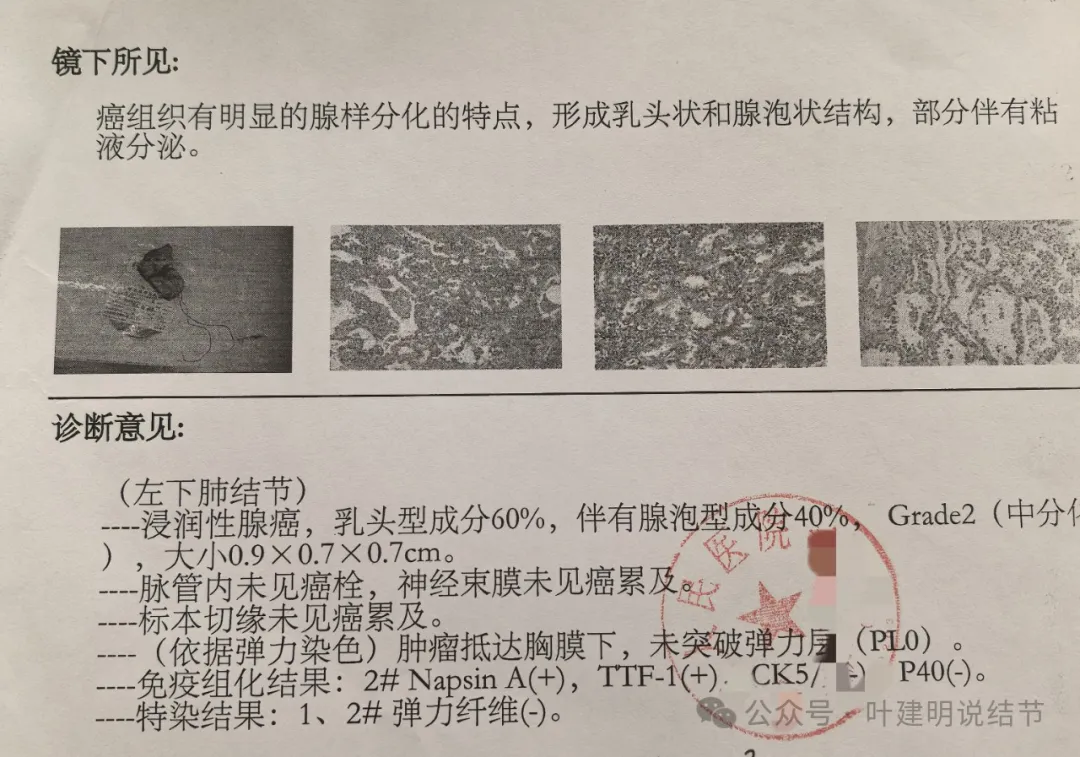

病理报告示浸润性腺癌,乳头成分60%,腺泡成分40%,中分化,大小长径是0.9厘米。脉管阴性、切缘阴性、未侵犯胸膜。

1厘米不到,中分化,又没高危因素,按术后辅助治疗指南是不需要靶向治疗或化疗的。那我觉得做基因检测没什么意义。本来就是为了指导术后辅助治疗。另报告上说的最大才4毫米的结节太小了,没有临床意义,按指南只需年度复查的,所以用不着过于关注。意见供参考!

我问结友是楔切还是叶切,因为手术前急着咨询我怎么切的事。当时不是已经明确告诉她先楔切,如果没有高危亚型的话,就加淋巴结采样,不要切肺叶。而且从影像上已经告诉她考虑是浸润性腺癌了的,我判断腺泡为主型可能性大。结果说是切了肺叶!

那之前的问诊不是白问了吗?有何意义呢?我是觉得很可惜的。结友回复说,当地医生没有认真谈手术方案,那你要自己提出来呀!医生只说先切一下,看看是不是恶性,结果术后就是肺叶切掉了!合乎指南吗?当然合规的,这是奉旨切肺叶呀!因为指南的表述就是:早期肺癌的标准术式是解剖性肺叶切除加淋巴结清扫术,是1A类证据级别的!

事后证明没有转移,也没有高危亚型,也没有高危因素,而且是实性的随访了3年了,有增大才考虑恶性予以手术的。位置这么边上,多可惜呀!但结友还在纠结咨询“左上叶尖段纤维条索状要不要紧?”。唉!

医生说这位置亚肺叶切除切缘不够!!这是啥判断?还说年纪比较轻,还做淋巴结清扫。当然清扫也没错,也是规范的。这该死的指南!!